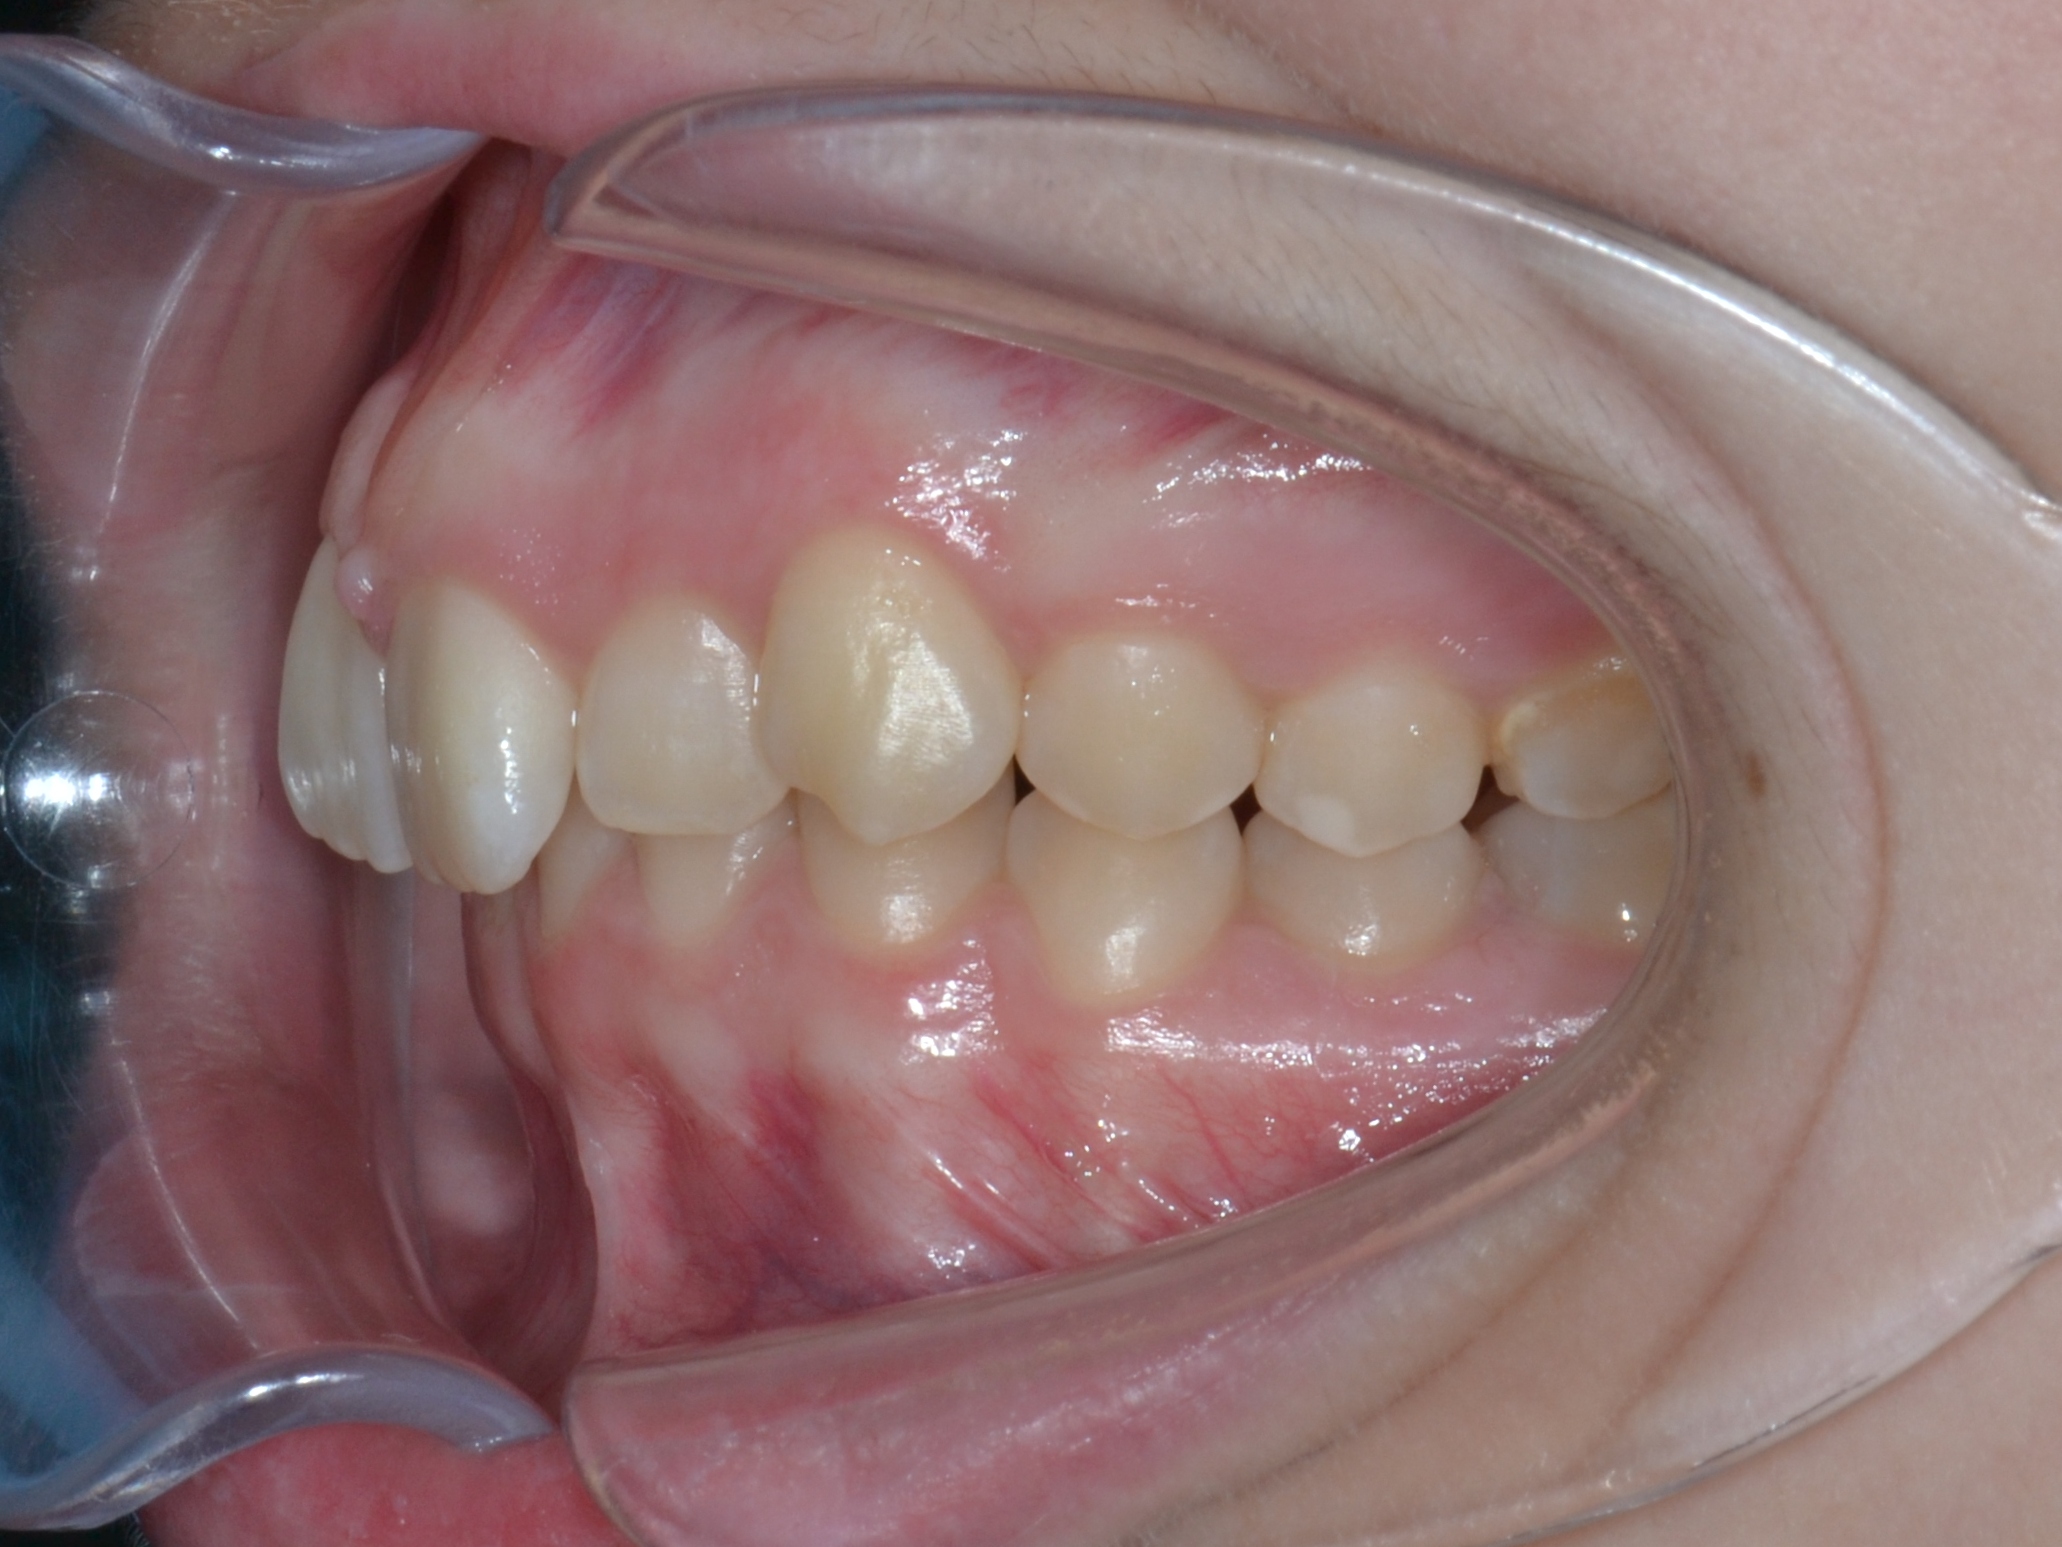

Выявленные проблемы

• Дистальная окклюзия ||(2)

• Глубокое резцовое соотношение

• Скученность фронтальных зубов

• Вестибулярное положение клыков

Брекет-система Ultra